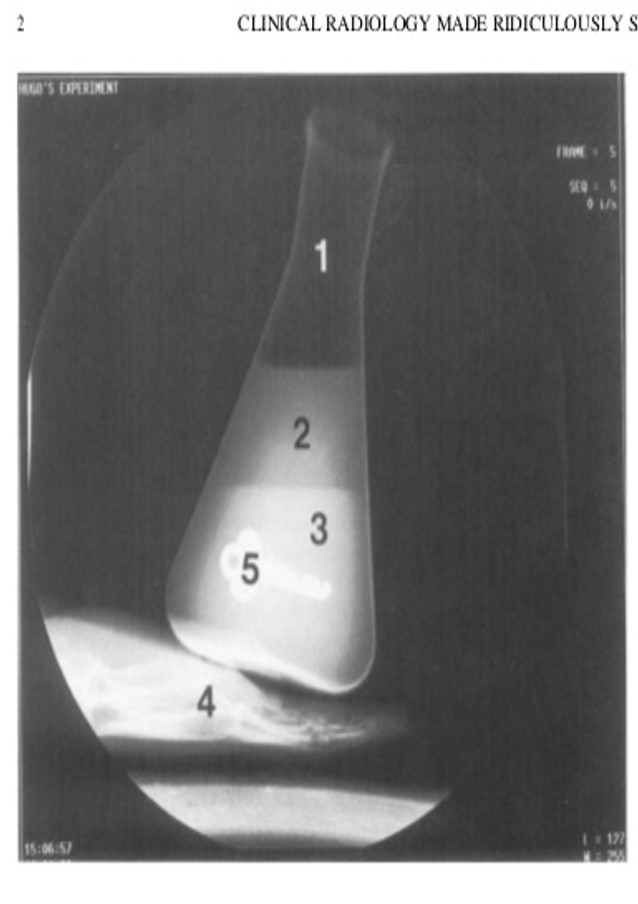

identify 1-5